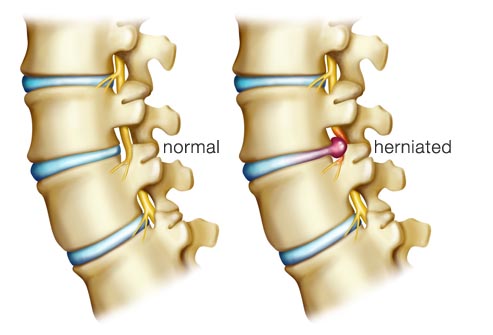

Back Pain Culprit: Herniated Disc

The spine’s vertebrae are cushioned by gel-like discs that are prone to wear and tear from aging or injuries. A weakened disc may rupture or bulge, putting pressure on the spinal nerve roots. This is known as a herniated disc and can cause intense pain.

The kind of back pain that follows heavy lifting or exercising too hard is often caused by muscle strain. But sometimes back pain can be related to a disc that bulges or ruptures. If a bulging or ruptured disc presses on the sciatic nerve, pain may run from the buttock down one leg. This is called sciatica.